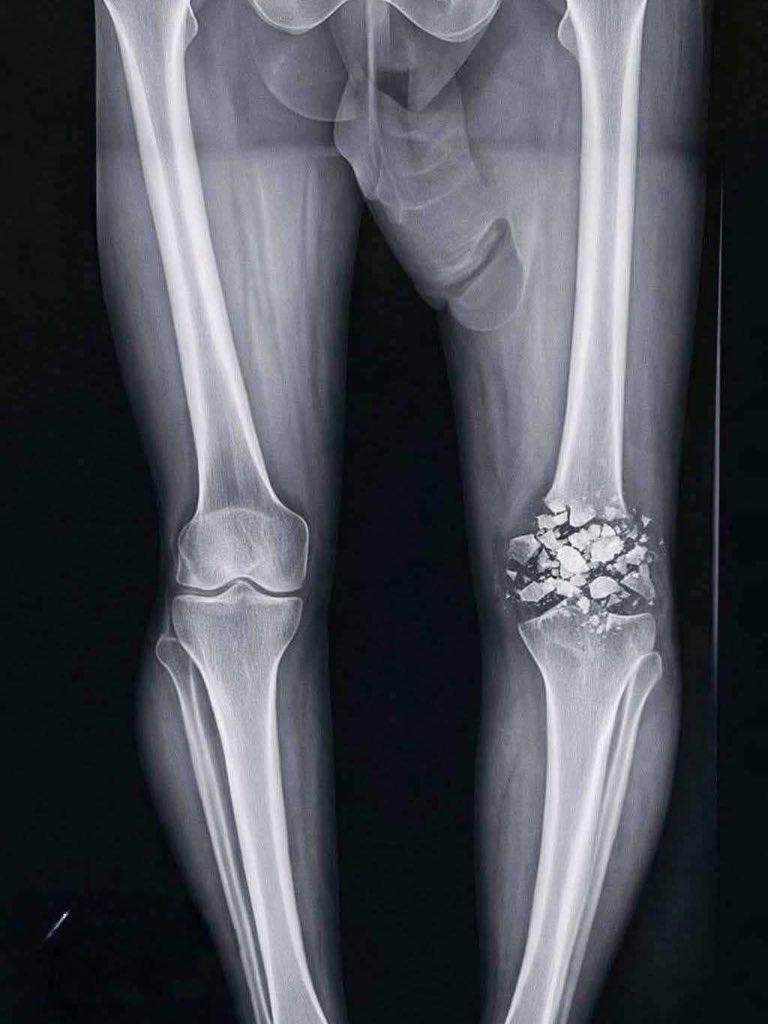

@Alexryu111 搞什麼,被車撞嗎? 這要一段很長時間才能好呢... 保重,朋友

◽ 左膝盖粉碎性骨折,一个月没去健身房了。 ◽ 来源:@m__anu_